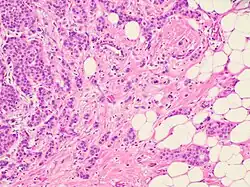

Histopathologic criteria

On microscopic evaluation carcinomatous cells are seen below the basement membrane of lactiferous ducts and invade into the surrounding breast stroma. Otherwise, there are no specific histologic characteristics, essentially making it a diagnosis of exclusion.[21] The histopathologic characteristics seen in these lesions are heterogenous. The cells of a lesion of invasive carcinoma NST may retain >70% ductal differentiation or appear completely undifferentiated. The tumor cells may be arranged in sheets, nests, cords, or singly distributed. They are pleomorphic (i.e., vary in size and shape). They usually have prominent nucleoli and multiple mitotic cells per magnified field of view, which are features generally consistent with cancerous cells. The surrounding non-ductal tissue, known as stroma, can range from none to abundant.[22][23]

Small inclusions of special features may be present within an invasive carcinoma NST tissue sample, but will be 'limited' (ie <10%). Carcinomas of mixed type will have a specialized pattern or lobular carcinoma in the majority (ie at least 50%) of the tumor and a non-specialized pattern in between 10-49% of the sample. Thus, such tumors will be called mixed invasive NST and special type or mixed invasive carcinoma NST and lobular carcinoma.[24]

Invasive ductal carcinoma of the breast. H&E stain.